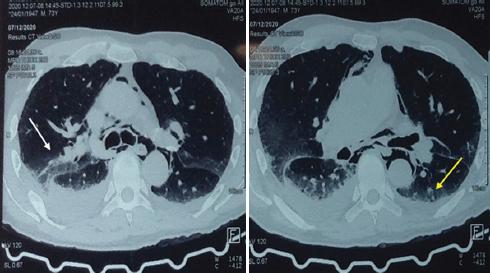

En la exploración física el paciente se encuentra despierto, escala de Glasgow 15 puntos, facies álgica, polipneico, con enfisema subcutáneo en la región supraclavicular y el tórax superior bilateral con crepitación, sin equimosis, con requerimiento de oxígeno suplementario por puntas nasales a 5 l/min, con disminución del murmullo vesicular en la región basal del hemitórax derecho y dolor abdominal a la palpación superficial y profunda en la región epigástrica, así como intolerancia al decúbito supino. El resto de la exploración no mostraba alteraciones, con los siguientes signos vitales: presión arterial 130/80 mmHg, frecuencia cardiaca 100 latidos por minuto, frecuencia respiratoria 20 respiraciones por minuto, temperatura 36.6 °C, saturación de oxígeno 96% y fracción inspirada de oxígeno 30%. Los parámetros de laboratorio fueron: hemoglobina 15.7 g/dl, hematocrito 45.9%, leucocitos 12.3 × 103/ml, glucosa 128 mg/dl, procalcitonina 34 ng/ml y troponina I < 0,04 ng/ml. El electrocardiograma mostró ritmo sinusal, frecuencia cardiaca 97 latidos por minuto, AQRS 0°, QRS 0.12 s y sin alteraciones del segmento ST. Se decidió realizar una radiografía de tórax, en la que se observó un enfisema subcutáneo en la región supraclavicular y ensanchamiento del mediastino (Fig. 1), y una tomografía computarizada de tórax con medio de contraste oral hidrosoluble, que confirmó el enfisema subcutáneo con extensión hasta la región escapular bilateral. También se observó neumomediastino bilateral, neumopericardio y fuga del medio de contraste hidrosoluble a nivel del tercio inferior del esófago hacia el mediastino medio, la cavidad pleural y el pericardio (Figs. 2 a 4). Se inició antibioticoterapia intravenosa (betalactámico y clindamicina).

Figura 3 Tomografía computarizada de tórax, ventana pulmonar (corte transversal), en la que se observan una zona de mayor densidad en el segmento posterior del lóbulo inferior derecho(flecha blanca) y derrame pleural bilateral de predominio derecho con ocupación aproximada del 20% (flecha amarilla).